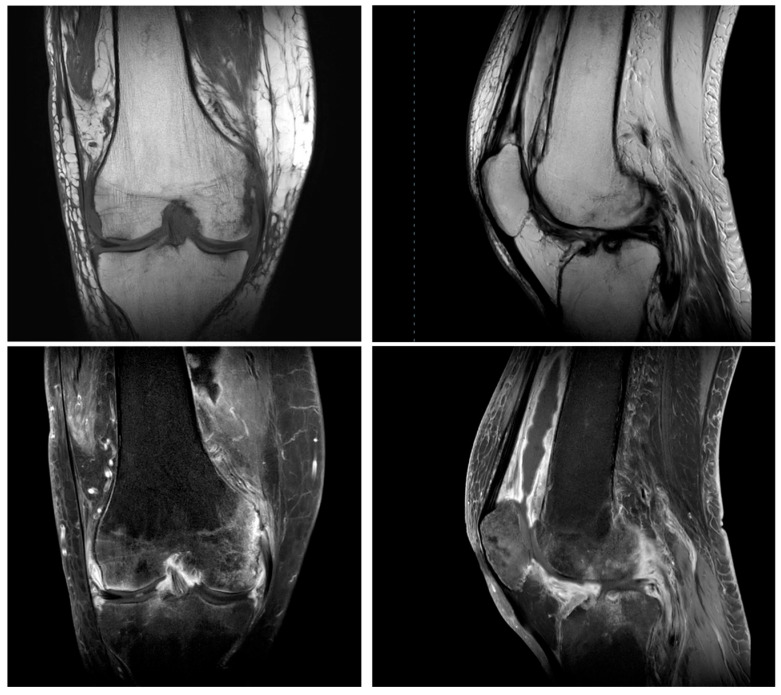

Introduction: Septic arthritis of the knee caused by the combination of Rothia mucilaginosa and Erysipelothrix rhusiopathiae is extremely rare. E. rhusiopathiae is a rare zoonotic pathogen that primarily affects individuals with occupational exposure to animals, while R. mucilaginosa can cause severe infections, particularly in immunocompromised patients. Case Presentation: A 59-year-old male underwent right knee arthroscopy in 2019 due to meniscal degeneration. Two weeks later, activity-related pain appeared. Magnetic resonance imaging showed proliferative synovitis, and joint aspiration revealed the presence of E. rhusiopathiae, which was treated with ciprofloxacin. As inflammation persisted, arthroscopic synovectomy was performed. Cultures revealed R. mucilaginosa and E. rhusiopathiae, prompting treatment with vancomycin and clindamycin. Despite repeated synovectomies, symptoms remained. After knee trauma in 2023, infection recurred. A two-stage total knee arthroplasty was performed in early 2024. At this time, another pathogen was isolated. At 12-month follow-up, the patient's function and alignment had improved significantly. Conclusions: The described case highlights the importance of anamnesis, early diagnostics, and knowledge about the possible resistances of rare pathogens to ensure appropriate treatment of the illness.